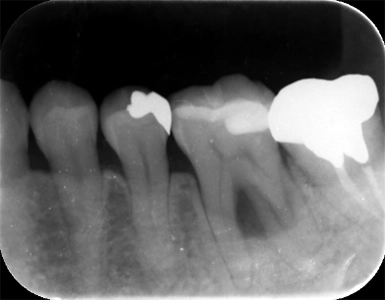

CASE1

歯周組織再生療法(保険診療)

術前

術後(1年後)

年齢・性別 50歳・女性

主訴 市の歯周病健診で歯周病を指摘された

診断名 広汎型慢性歯周炎ステージⅢグレードB

治療内容 歯周基本治療 歯石除去、ブラッシング指導により歯肉の炎症をできる限り改善し、その後歯周ポケットが深く歯槽骨の破壊が大きい部分に対して、歯周外科処置を行った。

治療期間 初診から歯周外科処置まで約5カ月、その後メインテナンス

費用 保険診療にて行う

リスク・副作用 術後の痛み、腫れ、出血が出ることがある

感染の可能性、腫れや再生不良が起こることがある

喫煙や清掃不良、炎症が重度の場合は組織再生の効果が十分得られないことがある

歯肉が引き締まる過程で知覚過敏が起こることがある。